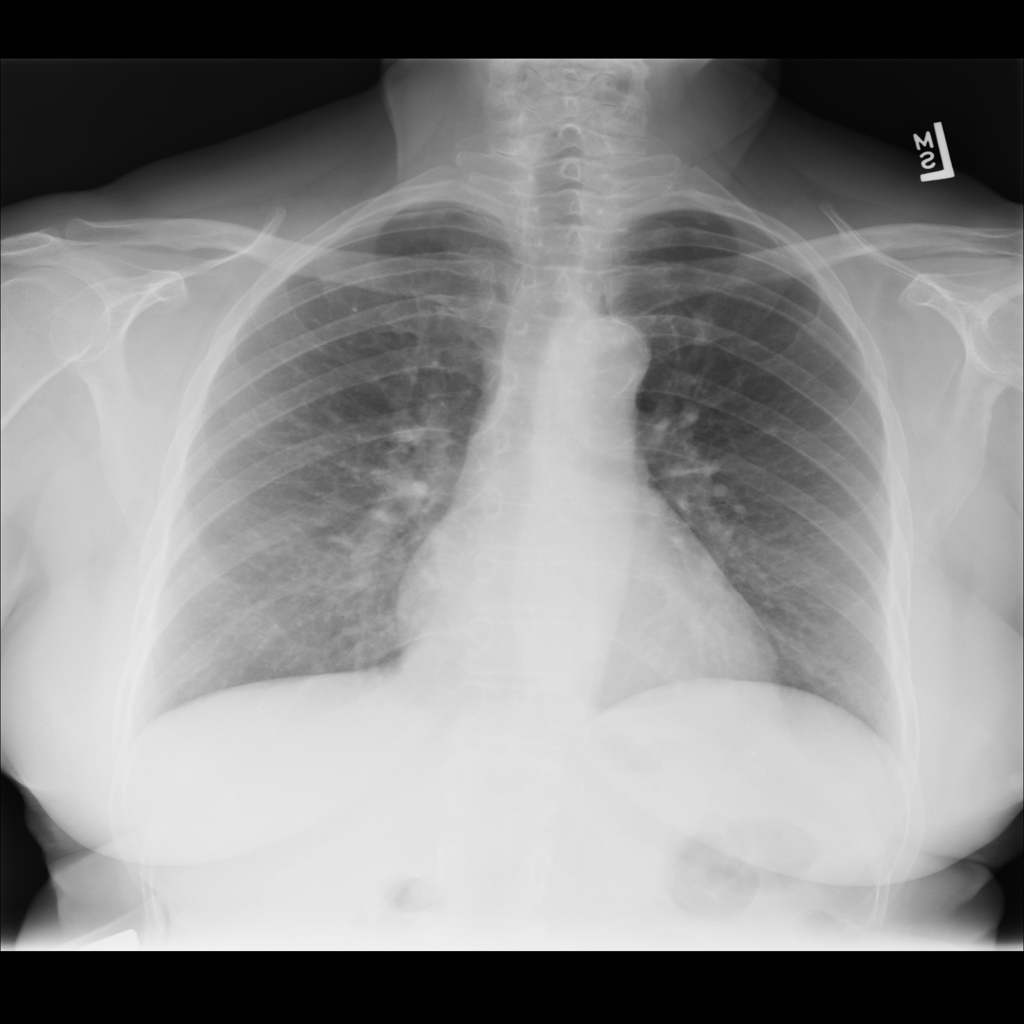

PAT-B0DB · IMG-003Emphysema

PAT-B0DB · IMG-003

PA